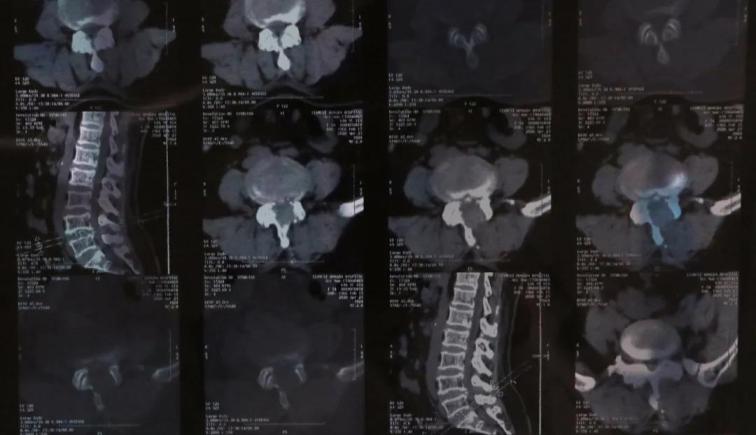

患者,女性,54歲,腰部疼痛伴雙下肢傳導(dǎo)痛五年,近半年癥狀逐漸加重,行走300米左右后疼痛難忍,生活質(zhì)量受到嚴(yán)重影響,多地醫(yī)院保守治療無效,來我院骨科,與患者交流病情后,為患者行脊柱內(nèi)鏡下單側(cè)入路雙側(cè)減壓(ULBD)椎管擴(kuò)大成型術(shù)。

術(shù)后患肢癥狀明顯減輕,功能恢復(fù)良好,下肢疼痛癥狀消失,左足背麻木感較術(shù)前明顯減輕,行走距離明顯增加。